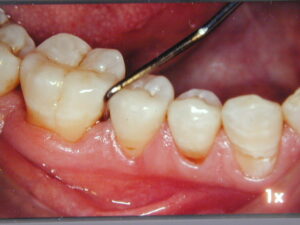

Mis on parodontiit

Parodontiit on krooniline haigus ja nagu teised kroonilised seisundid nõuab pärast aktiivse ravi lõppu eluaegset jälgimist. Olenevalt ravi raskusastmest (gingiviit, kerge-, mõõdukas- ja kaugele arenenud parodontiit), patsiendi kodusest hügieenist, veritsuse protsentuaalist, hammaste arvust, mille ümber on igemetaskud >4 mm, suitsetamise ja üldtervise staatusest, määratakse pärast aktiivse ravi lõppu individuaalne järelkontrollide graafik. Esimese aasta jooksul pärast ravi lõppu on see sagedasem.

Kontrollis ja hammaste puhastuses tuleks käia iga 3-4 kuu möödudes. Hiljem sõltub eelnimetatud teguritest järelkontrollide sagedus. Säilitav ravi on oluline nii patsientidele, kes teevad läbi korrigeeriva ravi faasi kui ka neile, kellel piirdutakse vaid mitte-kirurgilise raviga. Kuna eelnevalt parodontiiti põdenud on riskrühmas haiguse taastekkeks, on väga oluline regulaarselt igemete seisundil silma peal hoida.